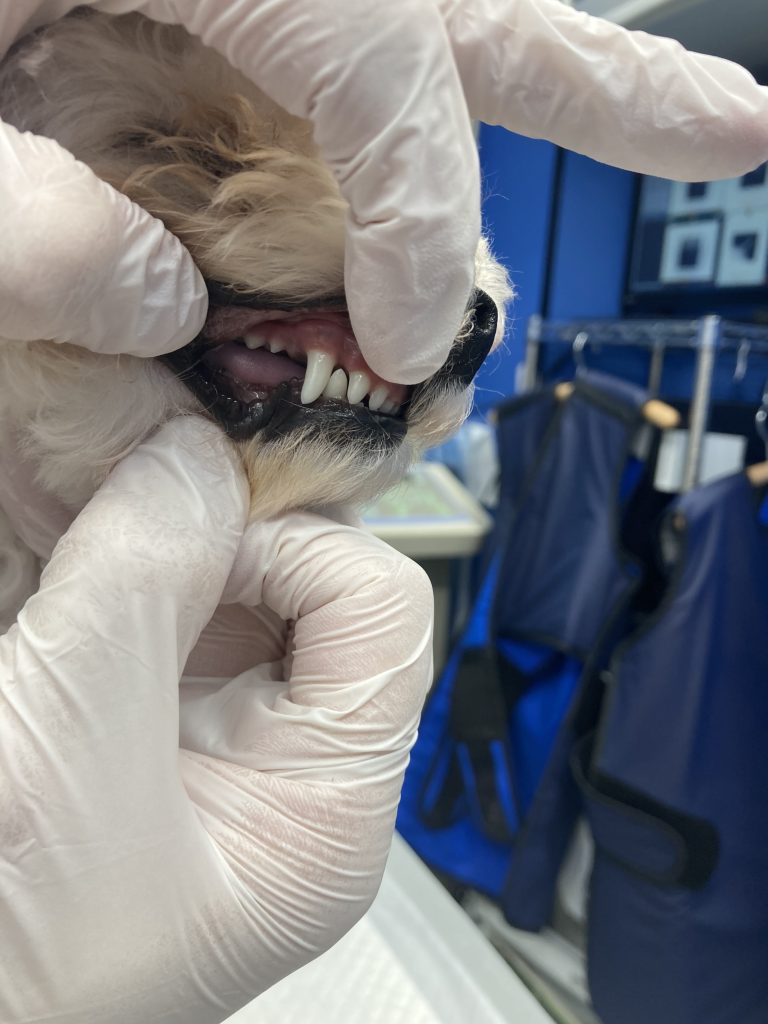

それでは、下の写真を見てみましょう。

下顎の犬歯が上顎の硬口蓋に当たってしまっています。

このように、対側の口腔粘膜や歯に当たってしまう歯は矯正の適応になります。